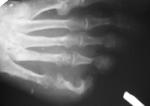

На рентгенограммах левой стопы (Рис. 2, 3, 4)в различных костях(преимущественно 5, 4 и 3 пальцы) определяются участки разрежения костной ткани округлой формы диаметром от 2-3 мм до 7-8 мм, окруженных склеротическим валом. Кости фаланги пятого пальца значительно деформированы.